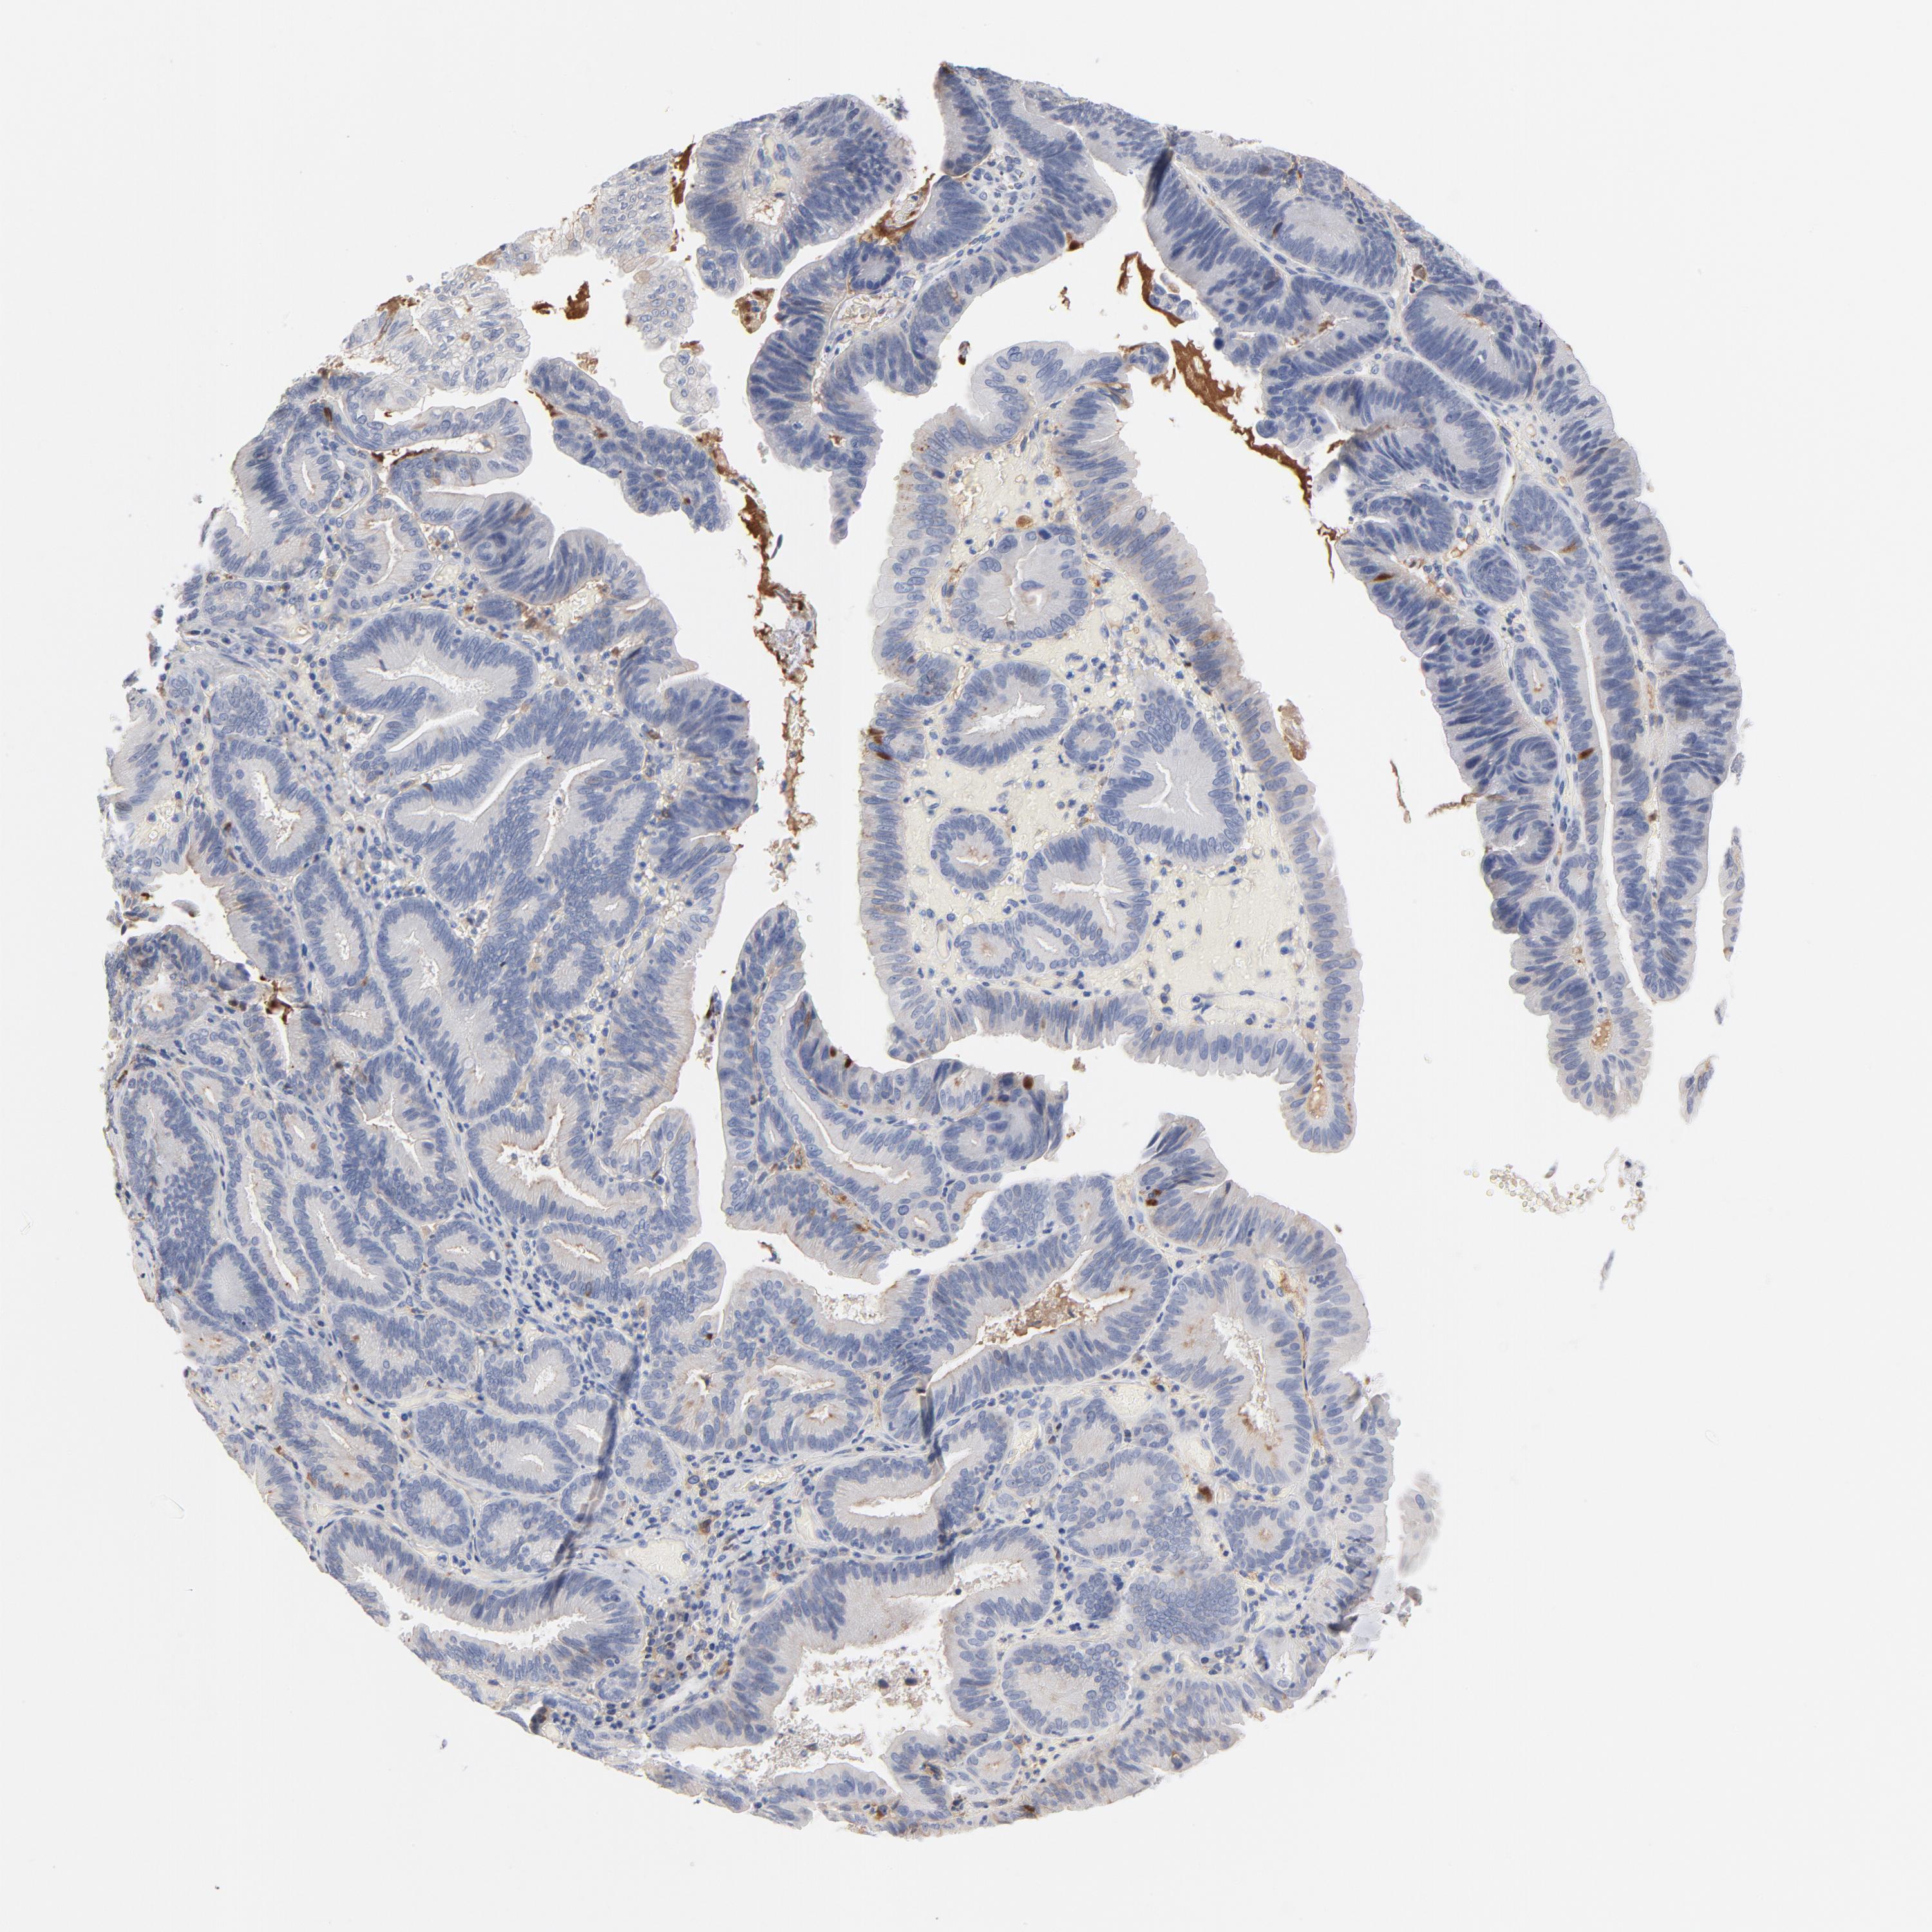

PANCREATIC CANCER - Protein expressioni

A mouse-over function shows sample information and annotation data. Click on an image to view it in a full screen mode. Samples can be filtered based on level of antibody staining by selecting one or several of the following categories: high, medium, low and not detected. The assay and annotation is described here.

Note that samples used for immunohistochemistry by the Human Protein Atlas do not correspond to samples in the TCGA dataset.

Antibody stainingi

Antibody staining in the annotated cell types in the current human tissue is reported as not detected, low, medium, or high, based on conventional immunohistochemistry profiling in selected tissues. This score is based on the combination of the staining intensity and fraction of stained cells.

Each image is clickable and will lead to virtual microscopy that enables deeper exploration of all samples and also displays staining intensity scores, fraction scores and subcellular localization as well as patient and tissue information for each sample.

Antibody HPA003607

Staining

High

Medium

Low

Not detected

Intensity

Strong

Moderate

Weak

Negative

Quantity

>75%

75%-25%

<25%

None

Location

Nuclear

Cytoplasmic/membranous

Cytoplasmic/membranous,nuclear

Adenocarcinoma, NOS

Adenocarcinoma, metastatic, NOS